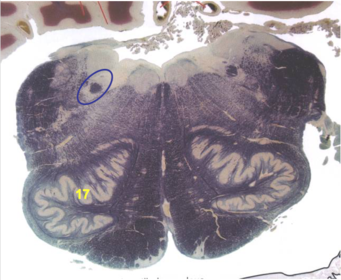

| CN IX | |

| Inferior cerebellar peduncle | |

| Inferior olivary complex | |

| Dorsal cochlear nucleus | |

| Inferior vestibular nucleus | |

| Medial vestibular nucleus | |

| Spinal nucleus of V | |

| Spinal tract of V | |

| Medullary pyramids | |

| Solitary nucleus | |

| ALS | |

| Medial lemniscus | |

| Medial longitudinal fasciculus | |

| Ventral cochlear nucleus | |

| Anterior spinocerebellar tract | |

| Central tegmental tract | |

| Olivary internal arcuate fibers | |

| Solitary tract | |